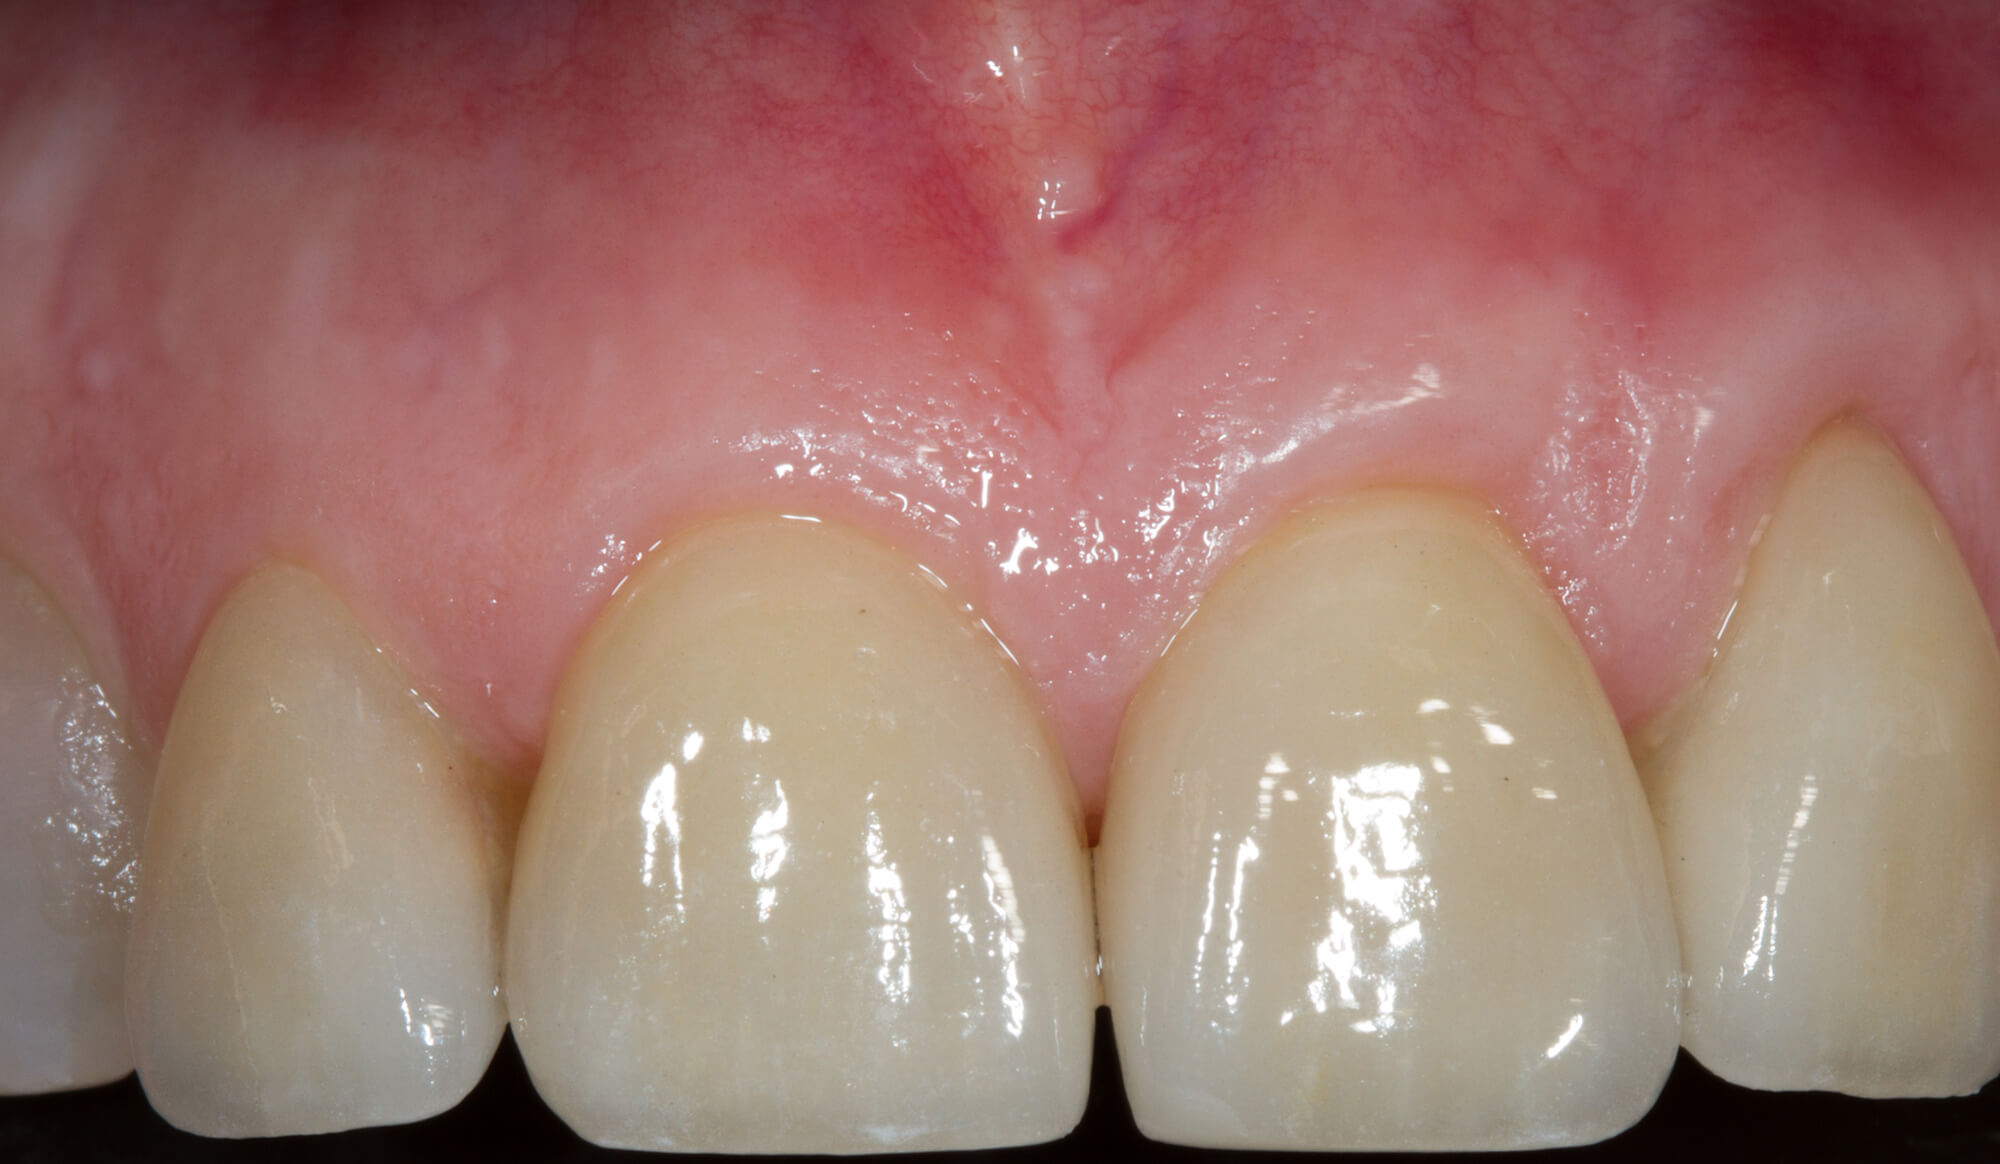

Riabilitazione complessa con applicazione di Faccette in Cermaica

In odontoiatria le faccette estetiche sono sottili lamine di ceramica o di resine composite che vengono applicate sulla superficie di denti sani per modificarne aspetto, colore e forma, talvolta anche per modificare parametri occlusali.

Questo è uno dei metodi di restauro dentale che richiede una preparazione minimale dei denti. L’unione fra dente e faccetta avviene mediante un cemento resina composito.

Le faccette quindi possono risolvere con un trattamento veloce e poco invasivo problematiche di tipo estetico che posso causare problemi anche emotivi soprattutto in pazienti giovani che da molti anni sono condizionati da denti pigmentati, o più piccoli del normale (conoidi), che influiscono sulla capacità di relazione con gli altri ragazzi.